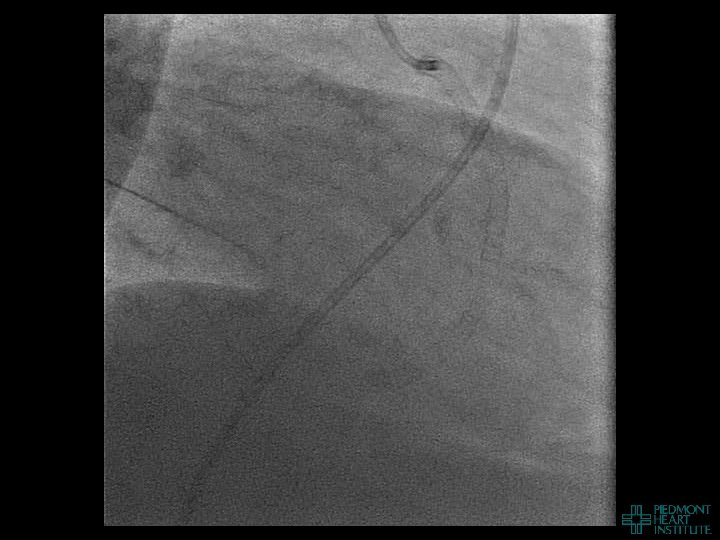

Case Example 2